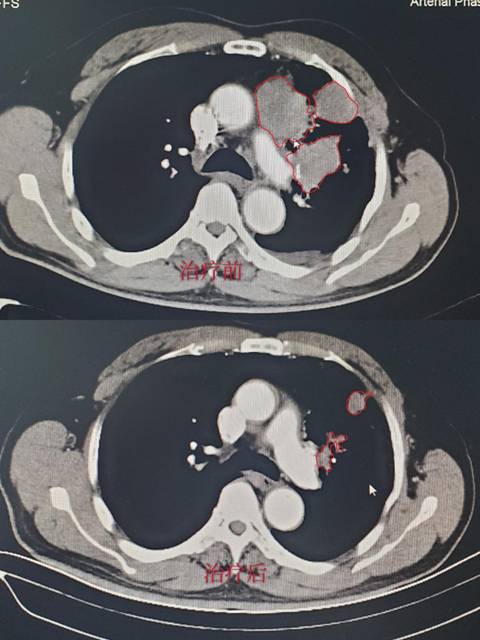

病例2:应某某,诊断为:左肺小细胞癌广泛期。治疗之前存在严重咯血及咳嗽,治疗3天后就停止咯血,咳嗽明显好转,经 2周期治疗后免费复查胸部CT,肿瘤缩小80%。(CT结果如下,红色线框内为肿瘤组织。)